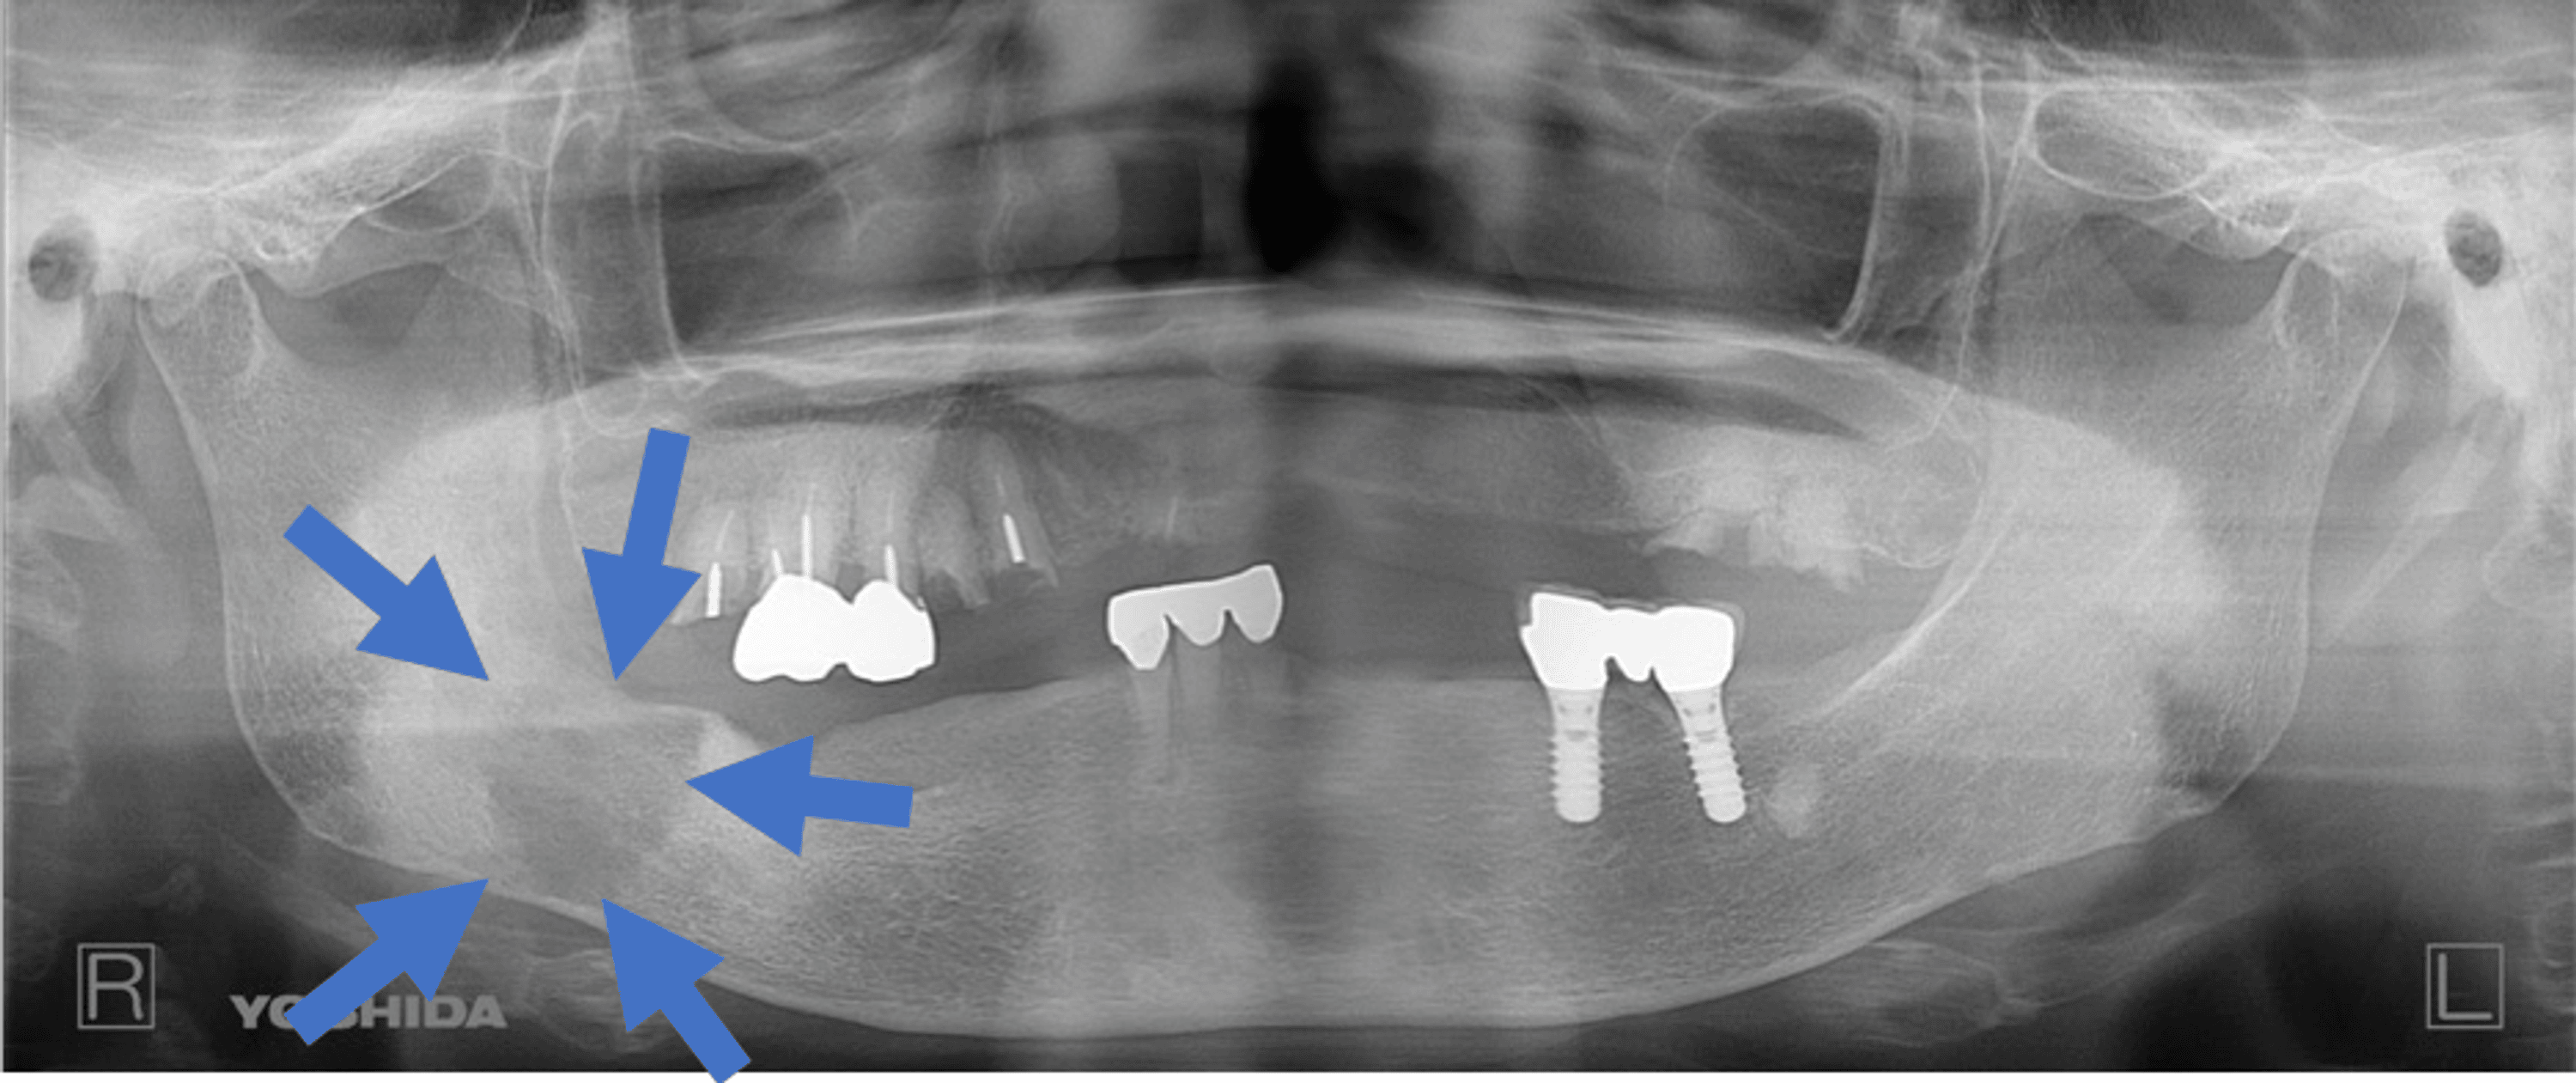

Spindle cell in a 64 years old male patient. Axial CT images... Download Scientific Spindle-Cell Sarcoma Jaw This diagnosis includes fibrosarcoma and sarcomas with indeterminate histomorphology, excluding melanocytic tumors and sarcomas that can be differentiated by histomorphology. Spindle cell carcinoma (scc) is a rare variant of squamous cell carcinoma characterized by elongated and pleomorphic. Spindle cell sarcoma (scs) is a malignancy, with the most recent surveillance, epidemiology, and end results (seer) data citing a total of 250. Spindle-Cell Sarcoma Jaw.

A Case of Spindle Cell Squamous Cell Carcinoma Manifesting in the Mandible Following Resection Spindle-Cell Sarcoma Jaw Feline maxillary sarcomas are aggressive spindle cell neoplasms that occur within the maxilla, palate and upper lip of cats. Spindle cell carcinoma (scc) is a rare variant of squamous cell carcinoma characterized by elongated and pleomorphic. This diagnosis includes fibrosarcoma and sarcomas with indeterminate histomorphology, excluding melanocytic tumors and sarcomas that can be differentiated by histomorphology. Spindle cell sarcoma (scs). Spindle-Cell Sarcoma Jaw.